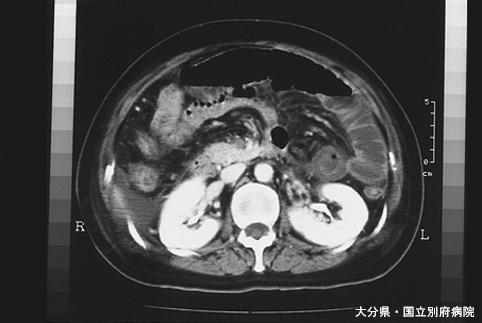

상장간막 정맥혈전증에 의한 소장 괴사의 수술

Oita Pref., 벳푸의료센터 (Dr. 大塚)

염증성 및 궤양성질환/허혈성 장염(혈전증 포함)

소장/2개 이상

CT

40이상